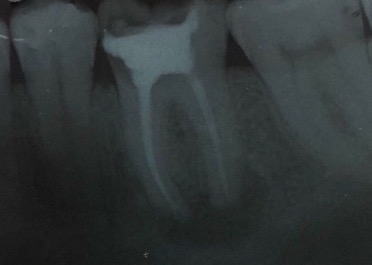

Capita spesso di incontrare denti già devitalizzati in maniera impropria che necessitano, seppur asintomatici, di essere ritrattati per evitare che i granulomi infetti visibili radiograficamente si evolvano riassorbendo tutto l’osso sottostante.